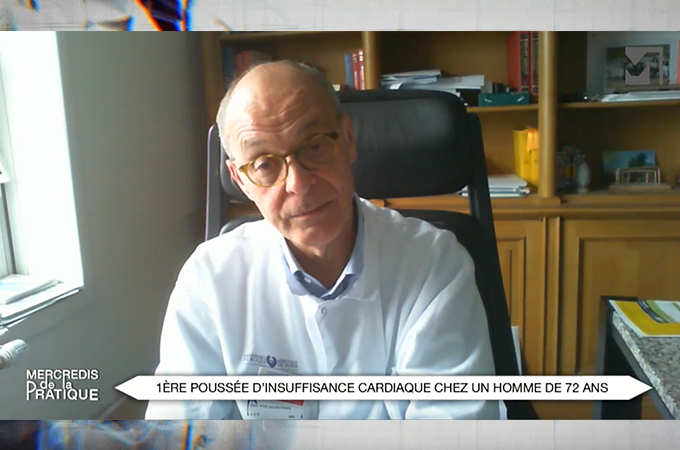

Le durvalumab a fait la preuve de son efficacité en traitement d’entretien du CBNPC grâce à l’étude PACIFIC. Mais, une étude coût-efficacité n’a pas apporté de résultats probants permettant de faire profiter de ce bénéfice tous le patients éligibles, larga manu. Des marges de négociations seraient-elles possibles ? D’après un entretien avec Christos CHOUAID.

Le professeur Christos CHOUAID, pneumologue et oncologue thoracique dans le service de pneumologie au Centre Hospitalier intercommunal de Créteil, précise que les cancers bronchiques non à petites cellules représentent 85% des 50 000 nouveaux cas annuels de cancers pulmonaires en Franc. Il rappelle qu’il existe trois catégories de CBNPC : les formes localisées opérables, les formes métastatiques qui ne sont éligibles ni à la chirurgie ni à la radiothérapie et les formes localement avancées, non métastatiques mais non opérables, qui représentent 15% des cas. Cette dernière forme est traitée par chimiothérapie et radiothérapie concomitante ou séquentielle pour les patients âgés ou plus fragiles. Christos CHOUAID fait référence à l’étude PACIFIC, en 2017, essai contrôlé versus placebo de phase 3, qui a évalué le rôle du Durvalumab, inhibiteur de PD-L1 dans le cancer du poumon non à petites cellules localement avancé, non opérable. Les patients avaient bénéficié d’une maintenance par durvalumab tous les 15 jours ou 1 mois pendant un an, alors qu’un second groupe avait reçu un placebo. Les résultats de cette étude avaient montré un gain de survie sans progression et de surie globale supérieur à 10%. A 5 ans, un patient sur deux était encore vivant et un tiers des patients n’avait pas progressé. Christos CHOUAID souligne qu’en termes de pertinence clinique, ces résultats sont intéressants et que ce traitement peut devenir le standard de prise en charge pour ces patient pendant un an.

Christos CHOUAID explique que l’étude actuelle a évalué le rapport coût /efficacité du traitement par durvalumab pendant un an après la chimiothérapie et radiothérapie. Il souligne l’originalité de ce travail au cours duquel les auteurs ont évalué le coût de cette prise en charge en rapport avec les années de vie gagnées en bonne santé dans quatre pays aux systèmes de santé différents (USA, Espagne, Singapour et Brésil). Ils ont montré que cette stratégie n’était pas coût-efficace et qu’il faudrait que le durvalumab soit moins cher, ce qui contredit des études antérieures qui démontraient que, compte-tenu du bénéfice, cette stratégie était coût-efficace. Christos CHOUIAD explique que ces discordances ont été discutées depuis l’étude PACIFIC en cernant mieux les patients éligibles à cette thérapie. En effet, les patients non-fumeurs et porteurs de mutations oncogéniques ne représentent pas de bons candidats. Il relève que dans cette étude, les auteurs ont inclus tous les patients. Il conclue donc qu’il doit exister une marge de négociation en termes de prix/volume, si cette prise en charge devient la stratégie standard. Pour lui, il est difficile de priver les patients d’un traitement qui fonctionne, en particulier les fumeurs.

En conclusion, le durvalumab en traitement d’entretien après chimiothérapie et radiothérapie dans les cancers bronchiques non à petites cellules, localement avancés et non opérables a fait la preuve de son efficacité. Malheureusement, son coût trop élevé risque d’en limiter son utilisation. Il est probablement possible d’entamer des négociations afin d’en faire bénéficier au moins les patients les plus répondeurs.